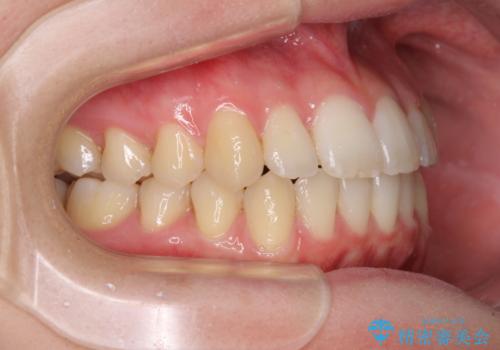

気になる前歯を整えたい インビザライン・ライトでの矯正治療

- ちょっとしたデコボコを整えたいとのことで来院された患者様です。

歯列不正は軽微であったため、インビザライン・ライトにより、費用を抑えて矯正治療を行うこととしました。

上下前歯の捻れが改善され、患者様には大変満足していただきました。